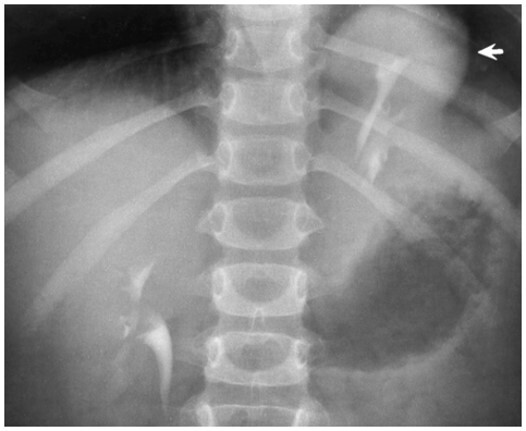

9

Q

What pathology is seen here?

A

Ectopic Kidney